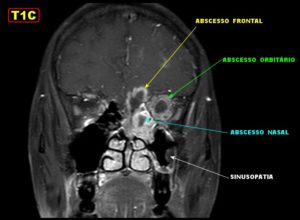

При отсутствии лечения возможен переход воспалительного процесса на близлежащие органы с развитием менингита, абсцесса мозга, неврита зрительного нерва.

Помимо боли и общего ухудшения самочувствия, воспаление клиновидной пазухи может привести к развитию таких тяжёлых заболеваний, как:

- Арахноидит;

- Менингит;

- Неврит зрительного нерва;

- Флегмона орбиты глаза;

- Абсцесс мозга и др.

Если заболевание не лечить, оно способствует развитию тяжёлых осложнений:

- хронизация процесса;

- переход воспаления на другие пазухи с формированием пансинусита, лечить который придётся очень долго;

- переход воспаления на глазницу с развитием абсцессов и флегмоны — их лечить только оперативно;

- патология черепно-мозговых нервов и соответствующие симптомы;

- нарушение зрения необратимого характера;

- переход воспаления на головной мозг с развитием осложнений — менингита и энцефалита.